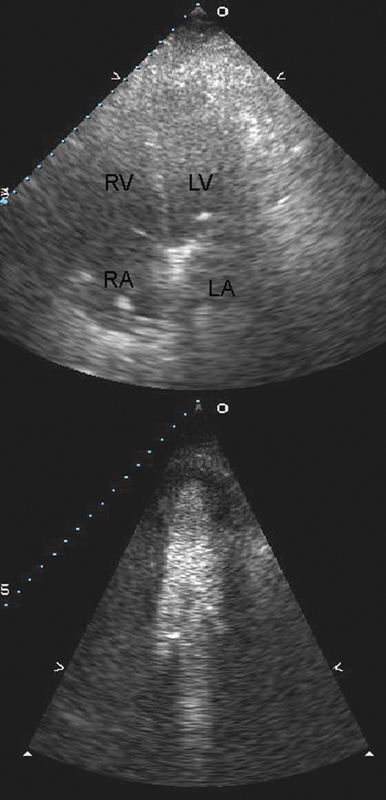

فحوصات تشخيصية لبعض امراض القلب والشرايين التاجية